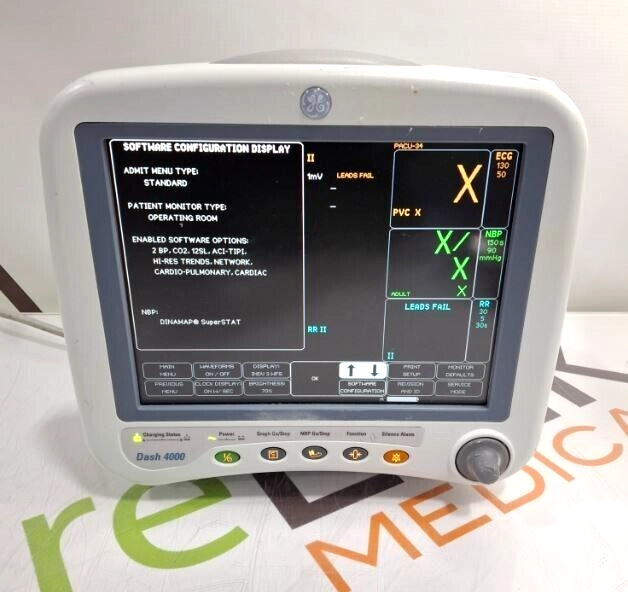

GE Healthcare Dash 4000 - Masimo SpO2 Patient Moni

$124.00

USD

GE Healthcare Dash 4000 - Masimo SpO2 Patient Moni

$124.00

USD

GE Dash 4000

$1,595.00

USD

GE Dash 4000

$1,595.00